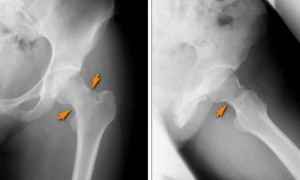

К сожалению, стрессовый перелом не всегда можно рассмотреть на рентгенологическом снимке, который сделан сразу после травмы. Только через две недели, с формированием костной мозоли, становиться видна линия перелома.

Особенно малоинформативны диагностические показатели при переломе в области бедра. Потому обязательно следует уточнить наличие физической активности. Хорошо провести диагностические тесты.

В случае перелома в области бедра, необходимо сделать рентгенограмму таза в нескольких проекциях. При дисбалансе энергетическом необходимо биохимическое исследование мочи и крови. Для правильной и своевременной диагностики лучше всего использовать МРТ с последовательностью STIR и сцинтиграфию костей.